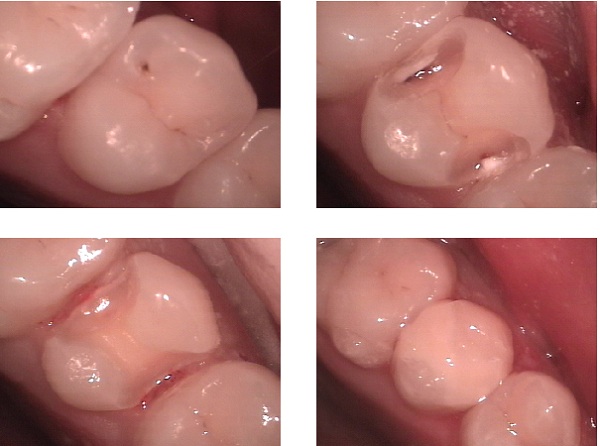

복합레진은 현재 임상에서 가장 많이 사용되는 심미수복재이다.[26] 환자들에게는 일반적으로 "치아색 충전재"로 설명되며, 치아 우식증과 외상으로 생긴 와동을 채우고, 치아 마모(비우식성 치아 표면 손실)를 수복하며, 치아 사이의 작은 틈을 메우는 데 사용될 수 있다. 또한 크라운과 인레이를 제작하기 위한 간접 수복으로도 사용된다.

치아 준비 후, 얇은 프라이머 또는 접착제가 사용된다. 현대의 광중합 복합 레진은 불투명도에 따라 결정되는 비교적 얇은 층으로 적용되고 경화된다.[13] 일부 경화 후, 최종 표면은 모양을 잡고 연마된다.